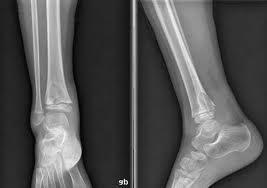

近年来肺外结核病人数正在逐年上升,除了乏力、低热、痰中带血的“肺结核”外,淋巴结结核、骨结核、肠结核、肾结核等正在侵袭着人们的健康。很多人在诊断出骨结核之后都非常奇怪,这个结核为啥会长在了骨头上:

结核病是人体感染结核杆菌后引起的。很多老百姓以为,结核病是肺部的问题,其他地方怎么可能“生出”结核来?其实,这种认识存在很大误区。结核病不仅包括“肺结核”,还包括“肺外结核”。除了肺部,骨头、淋巴、脊柱等部位,都是结核杆菌喜欢“光顾”的地方。>>>>推荐阅读:骨结核的病因

不久前我院接诊了一位骨结核病人,该病人之前一直有腹痛症状,半年前才到医院就诊,CT检查发现腹腔内有肿块,穿刺提示是结核。之后立即住院治疗,病势快速凶险,3个月前随即出现腰痛,拍片后发现胸椎、腰椎、颈椎均发生病变,背部已经弯曲无法伸直。

结核杆菌在组织细胞含氧量相对贫乏的骨骼里生长缓慢,毒性也较弱,因此症状并不明显。就像病人早些年前仅凭腹痛很难跟结核联系上,因而不重视耽误了治疗。